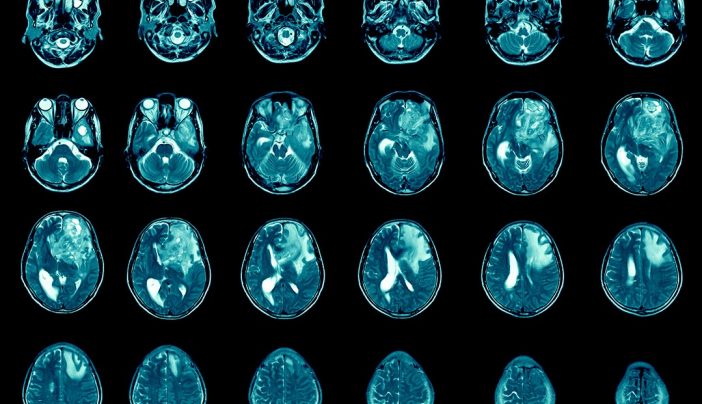

Glioblastoma is the most frequent type of malignant brain and other central nervous system CNS tumour accounting for 477 of all cases. Your symptoms will be well managed but if not you should speak to your team.

Stage 4 Glioblastoma Multiforme. Based on the signs and. Due to a decrease in level of consciousness and cognitive impairment assessment of clinical signs and symptoms such as headache at the end of life is difficult.